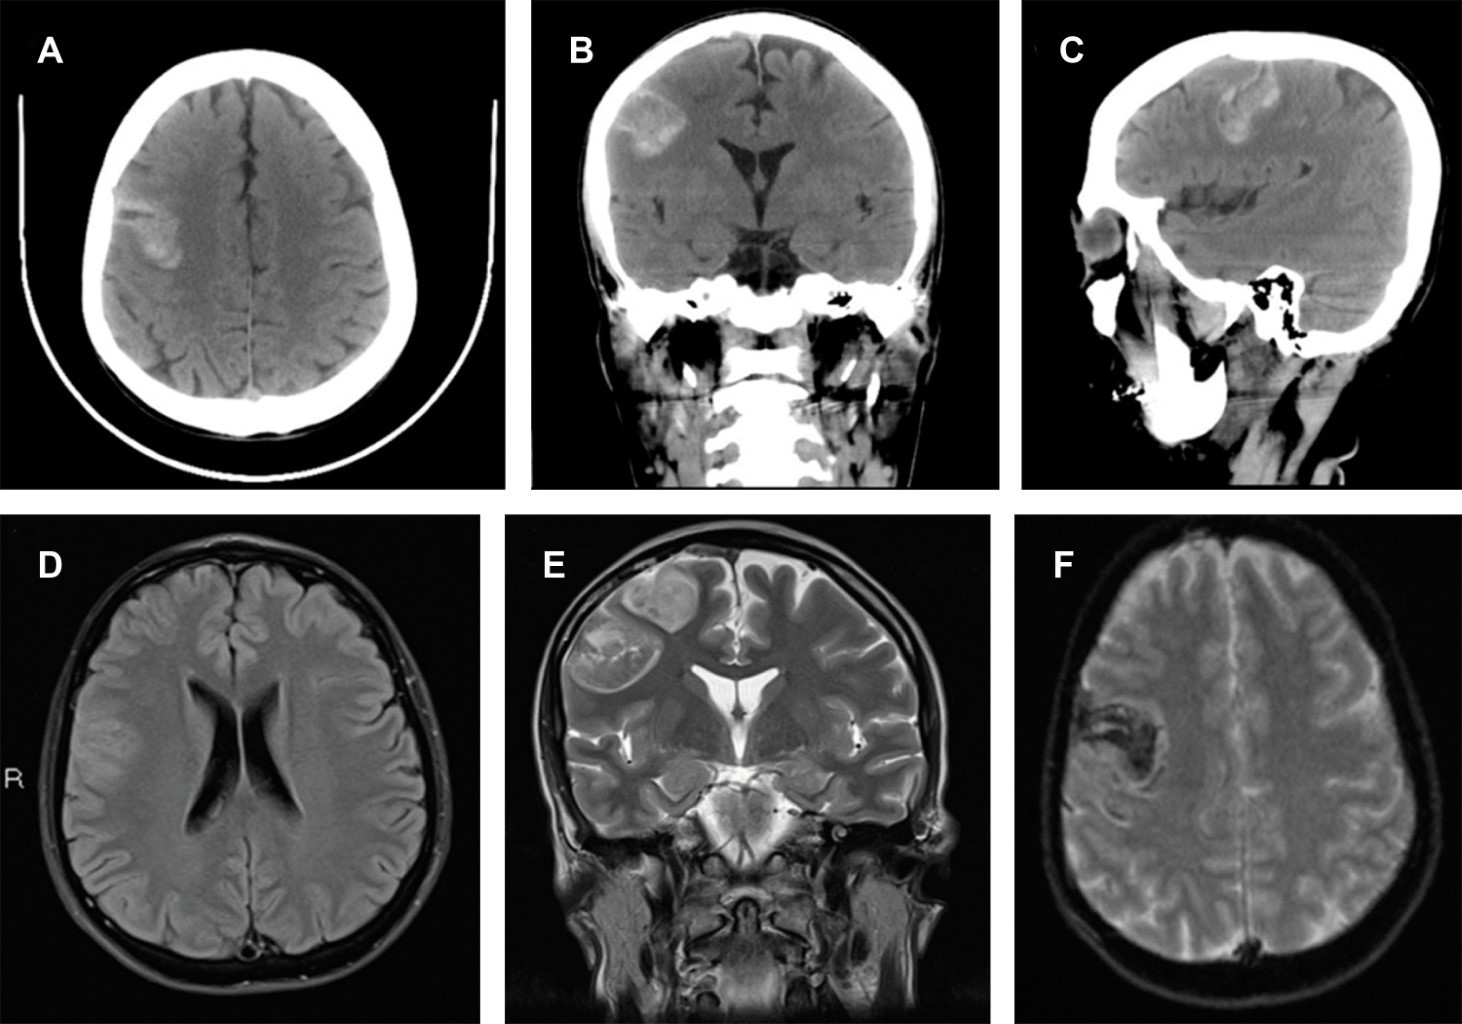

Introduction: systemic lupus erythematosus (SLE) is one of the most common autoimmune diseases; regarding its cerebrovascular effects, most reports indicate subarachnoid hemorrhage and rarely cerebral hemorrhage (CH). Case report: a 44-year-old female presented with non-traumatic cerebral hemorrhage (CH) as the debut of SLE. The patient was treated for CH, and coincidentally, multisystem involvement and severe thrombocytopenia were discovered, which allowed the diagnosis of SLE. Neuroimaging tests did not discover vascular malformations. Conclusions: CH is an uncommon presentation in SLE.

Figure 1